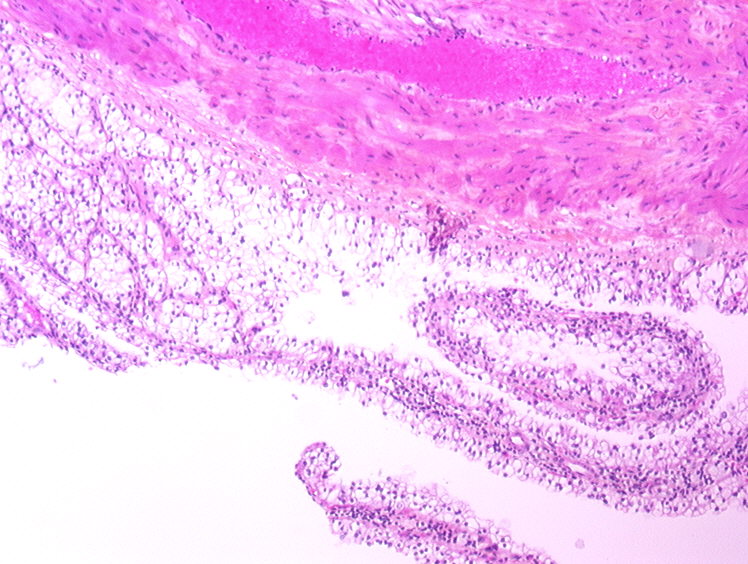

Consensus grade: WHO/ISUP grade 1

multilocular cystic clear cell carcinoma, very typical